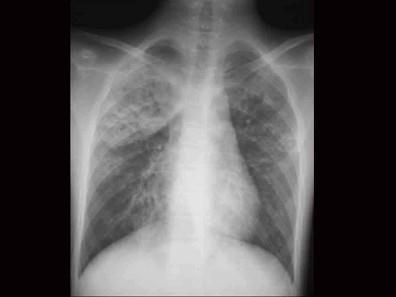

问题 患儿11个月,突发高热4天,烦躁,咳嗽频繁,呻吟,发病前3天有皮肤破损及感染史,肺部有散在中、细湿啰音,胸部X线可见斑点状结节阴影,见图,血象白细胞总数增高,核左移,该患儿最可能诊断为 ( )

选项 A、呼吸道合胞病毒性肺炎 B、肺炎链球菌肺炎 C、腺病毒性肺炎 D、支原体肺炎 E、金黄色葡萄球菌性肺炎

答案 E